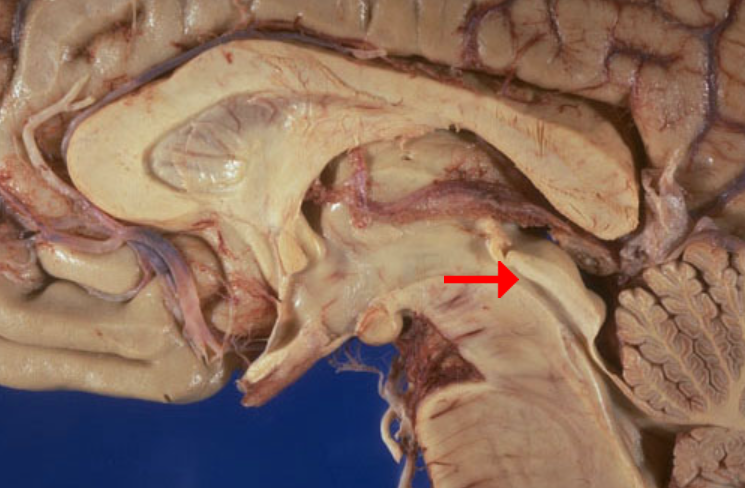

Label this brain part

Aqueduct of Sylvius

Label this brain part

Tectum (of midbrain)

Label this brain part

Fornix

Label this brain structure

Caudate nucleus

Label this brain structure

Putamen

Label this brain structure

Globus pallidus

Label this brain structure

Amygdala

Label this brain structure

Septum pellucidum

Label this brain structure

Optic chiasm

Label this brain structure

Cingulate gyrus

Label this brain structure

Substantia nigra

Label this brain structure

Optic tract

Name this brain structure

Hippocampus

Label this brain structure

Cerebral aqueduct

Label this brain structure

Superior colliculi

Name this brain structure

Fornix

Label this brain structure

Pineal gland